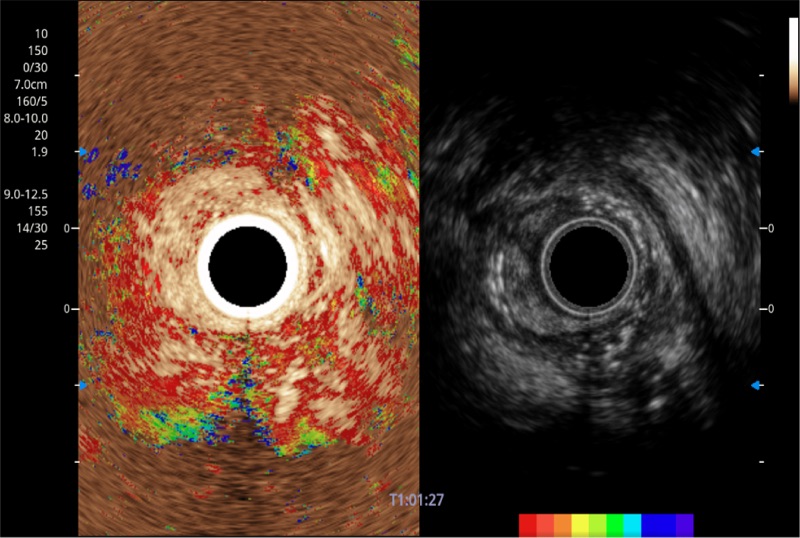

可人为将灰阶图像转变成彩色的显示方式,增强人眼对于不同回声强度的敏感度,主观上增加了图像分辨率

微米成像技术提升了对组织斑点噪声信号的抑制能力,并进一步强化边界信息,从而获得信噪比更优、边界更清楚锐利的图像

随着组织深度的变化,超声接收频率进行智能匹配跟踪,确保图像中、远场良好的穿透力以及整场一致的分辨力,从而得到均一的画质

食管内间质瘤清晰显像

清晰显示胆总管及周围血管分布

肝左叶和肝静脉的横截面